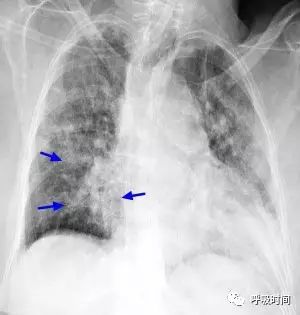

图 6 肺渗出性病变影——肺下叶支气管肺炎